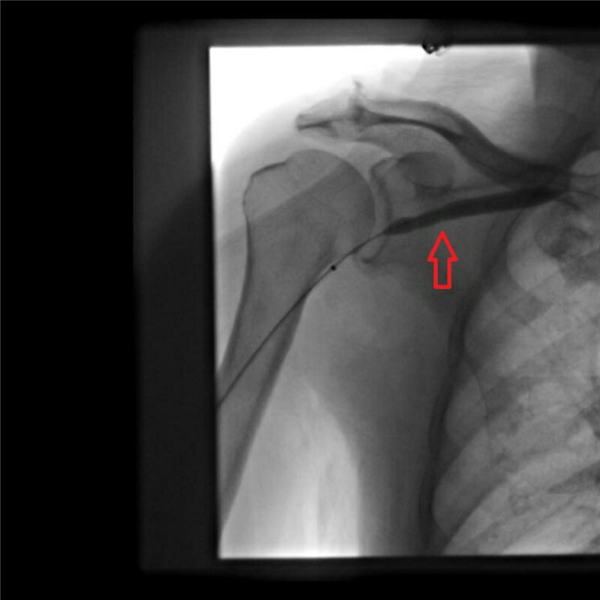

陈力强和赵庆和两位主任经过精心研讨方案,首先通过血管造影,发现右上肢动静脉瘘到上腔静脉共有三处血管明显狭窄(下图红色箭头所示),特别是右锁骨下静脉汇入上腔静脉处更明显,此处血管狭窄造成透析时血液回流障碍、右肩局部血管压力增高,由此引发右肩疼痛。